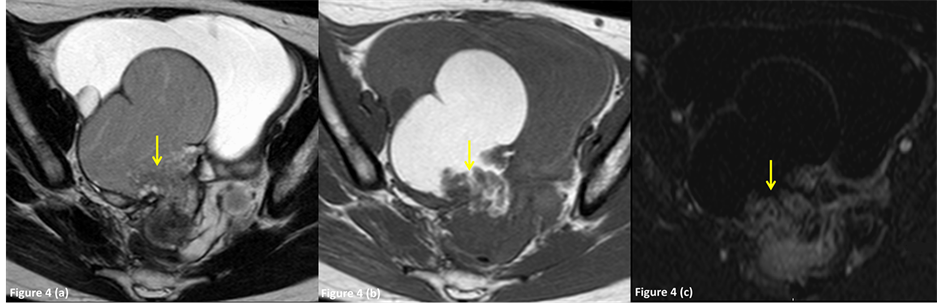

Figure 4. A 28-year-old female with benign endometrioma in the right ovary, which was preoperatively diagnosed as an endometrioma with malignant foci by MR imaging (group 3). (a) Axial T2-weighted image shows a diffusely hyperintense right adnexal mass (arrow) and a hyperintense mural nodule in the hypointense cyst wall. (b) Axial fat-suppressed T1- weighted image shows a hyperintense adnexal mass and a hypointense mural nodule (arrow). The attached angle of the mural nodule to the cyst wall was 114 degrees (obtuse angle). (c) Axial subtraction image shows intense enhancement of the mural nodule (arrow).

The characteristics of the mural nodules are summarized in Table 2 and Table 3. Mural nodules were associated with 3 (2.0%), 9 (100%), 17 (100%) and 0 (0%) lesions in groups 1, 2, 3 and 4, respectively (Figures 2-4). Of the 45 ovarian lesions, 20 were papillary and 25 were rounded. The shapes of the nodules were as follows (papillary vs. rounded): 0 vs. 7 lesions in group 1; 11 vs. 5 lesions in group 2; 9 vs. 13 lesions in group 3; and 0 vs. 0 lesions in group 4. The mean maximum diameter of the mural nodules was 5.1 ± 4.2 mm in group 1, 23.6 ± 19.7 mm in group 2 and 9.8 ± 6.1 mm in group 3: there were significant differences between groups 1 and 2 (p = 0.009) and between groups 2 and 3 (p = 0.054), but not between groups 1 and 3 (p = 0.149) (unpaired t-test with the Bonferroni correction). One case showed mural nodules (size: 3 × 2.4 cm) (Figure 4); in this case, preoperative MR images strongly suggested malignant lesions, however, the mural nodules were pathologically only granulomatous tissue.

On T1-weighted images, the mural nodules were hyperintense in one lesion (14%) in group 1 (Figure 2) and one (5%) in group 3, and hypointense in 6 (86%), 16 (100%) and 21 (95.5%) lesions in groups 1, 2 and 3 (Figure 3, Figure 4), respectively. On T2-weighted images, the mural nodules were hypointense in 7 (100%), 2 (13%) and 13 (59%) lesions in groups 1, 2 and 3 (Figure 2), respectively, and hyperintense in 0 (0%), 14 (88%) and 9 (41%) lesions in groups 1, 2 and 3 (Figure 3, Figure 4). In our study, only 9 of 26 cysts with enhanced nodules (34.6%) were diagnosed as pathologically malignancy.